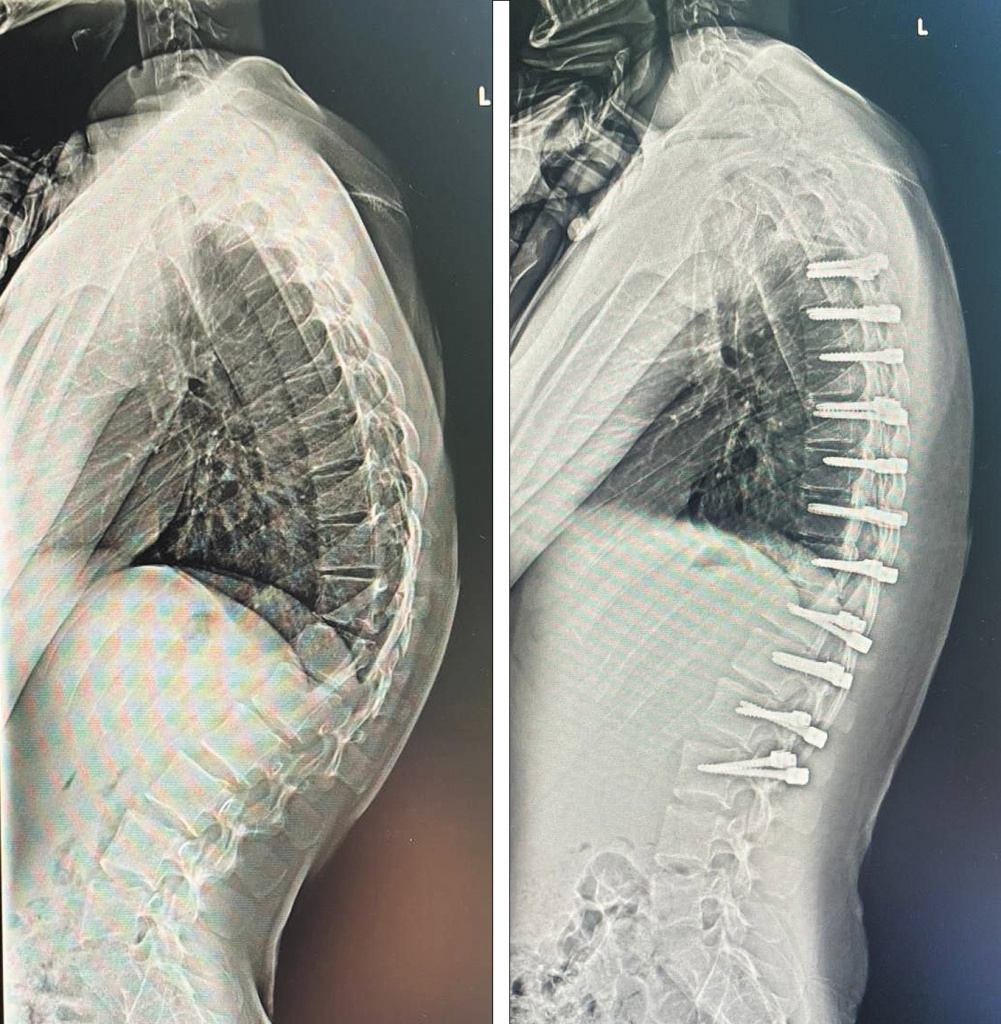

До и после операции

До и после операции по устранению кифоза. Фото: пресс-служба ДГКБ Св. Владимира